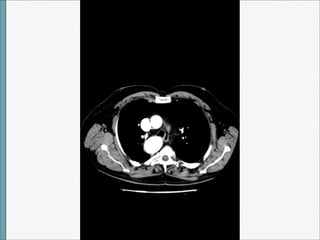

TAC

Arco Aórtico Derecho

1)CON ARTERIA SUBCLAVIA IZQUIERDA ABERRANTE